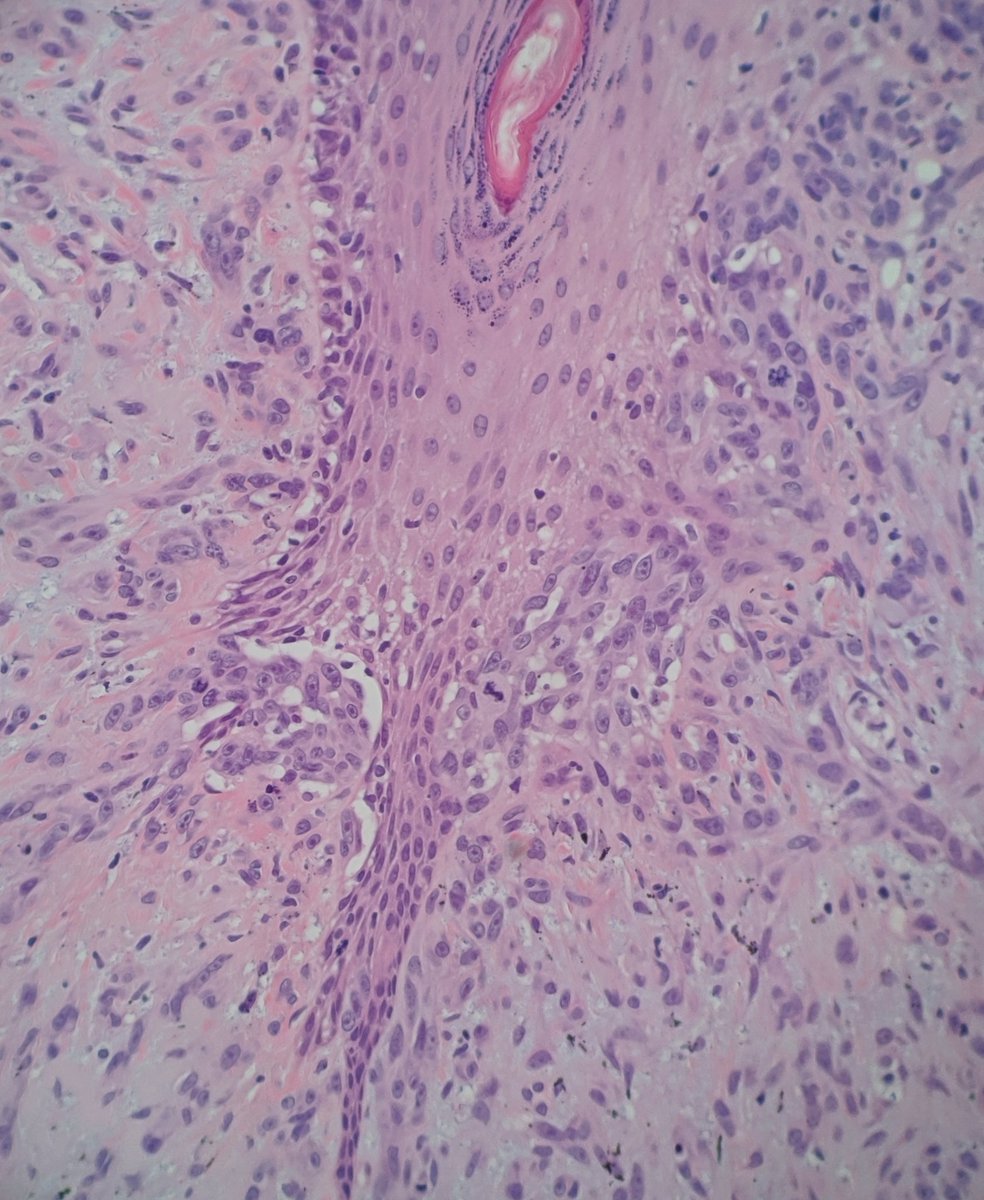

One typical feature of NTRK1 fusion Spitz lesions is a "nest of nests" pattern - what looks like a nest at low power turns out to be smaller nests rammed together at higher power. IHC is pan NTRK. #dermatology #dermpath #pathology